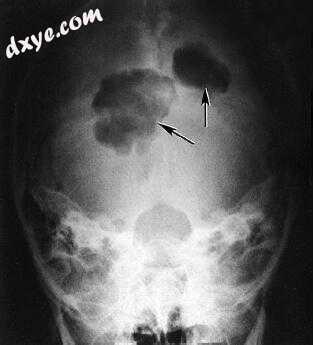

图-1. 一名32岁女性患有多种嗜酸性肉芽肿。 颅骨的两个溶解性病变显示出斜角(箭头)和非硬化边缘,这是这种疾病的典型特征。

2.jpg